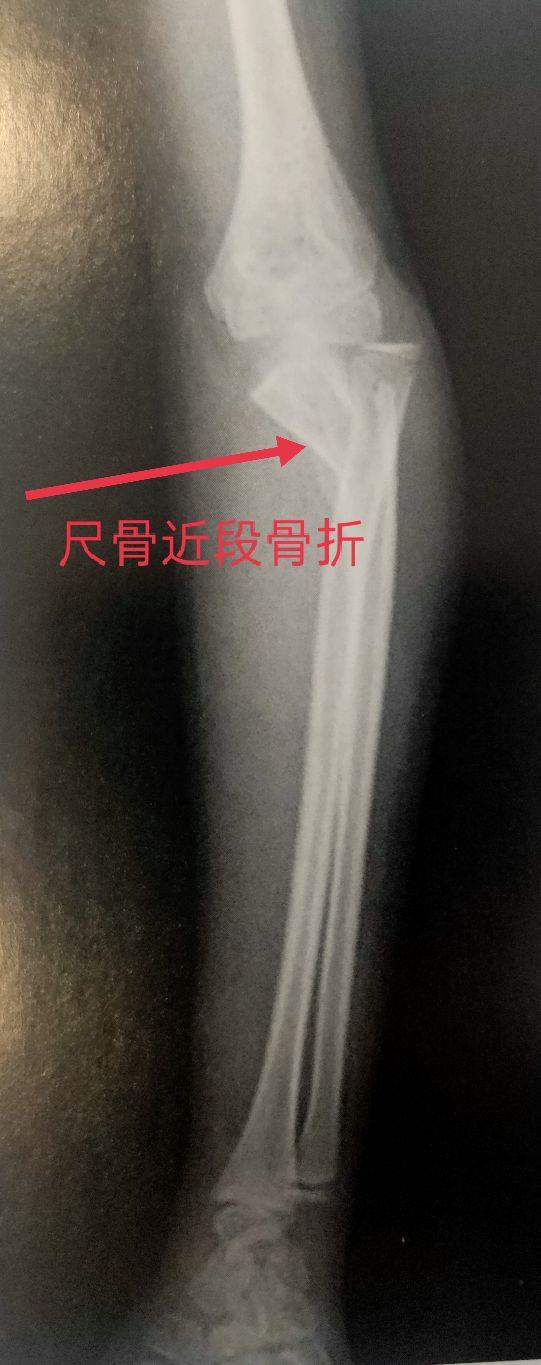

四、尺、桡骨骨折X线片

尺骨桡骨骨折以桡骨远端骨折多见。其次是尺骨桡骨双骨折,多发生于青少年。